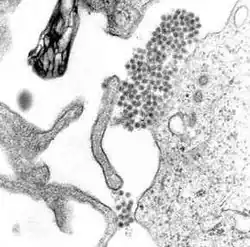

Wirus dengi (DENV) należy do wirusów RNA. Zalicza się go do rodziny Flaviviridae i rodzaju Flavivirus, do którego zaliczają się także wirus żółtej gorączki, wirus zachodniego Nilu, St. Louis encephalitis virus, wirus japońskiego zapalenia mózgu, wirus kleszczowego zapalenia mózgu, wirus gorączki lasu Kyasanur i wirus omskiej gorączki krwotocznej[7]. Większość z nich przenoszą stawonogi (komary i kleszcze), w związku z czym określa się je mianem arbowirusów (arthropod-borne viruses – „wirusy przenoszone przez stawonogi”)[7].

Genom wirusa dengi zawiera około 11 000 zasad azotowych, kodujących 3 różne typy cząsteczek białkowych tworzących cząstkę wirusa nazywaną wirionem: C, prM i E i 7 innych : NS1, NS2a, NS2b, NS3, NS4a, NS4b, NS5, spotykanych jedynie w zainfekowanych komórkach gospodarza i koniecznych dla replikacji wirusa[21][22]. Występują 4 znane wcześniej odmiany wirusa, nazywane serotypami. Określa się jako DENV-1, DENV-2, DENV-3 i DENV-4[12]. W 2013 roku opisano kolejny[23]. Różnice pomiędzy nimi opierają się na antygenowości[24].

Dostawszy się pod skórę, wirus dengi wiąże się z biorącymi udział w identyfikacji patogenu komórkami Langerhansa[36]. Białko wirusa wiąże się z białkiem powierzchniowym komórki Langerhansa, zwłaszcza lektyną typu C zwaną DC-SIGN, receptorem mannozy i CLEC5A[21]. DC-SIGN, niespecyficzny receptor obcych cząstek obecny na komórkach dendrytycznych, wydaje się być głównym punktem zaczepienia umożliwiającym wirusowi wtargnięcie do komórki[22]. Komórka zmierza wtedy do najbliższego węzła limfatycznego. W tym czasie genom wirusa ulega translacji w otoczonych błoną pęcherzykach siateczki śródplazmatycznej, gdzie należący do komórki gospodarza aparat syntezujący białka produkuje nowe białka wirusowe, które biorą udział w replikacji RNA wirusa i tworzeniu nowych wirionów. Niedojrzałe wiriony transportowane są do aparatu Golgiego, gdzie pewne ich cząsteczki białkowe zyskują niezbędne łańcuchy sacharydowe. Teraz już dojrzałe wiriony pączkują na powierzchni zainfekowanej komórki, ulegając wydaleniu poprzez egzocytozę. Są wtedy zdolne do wnikania do kolejnych leukocytów (monocytów, makrofagów)[21].